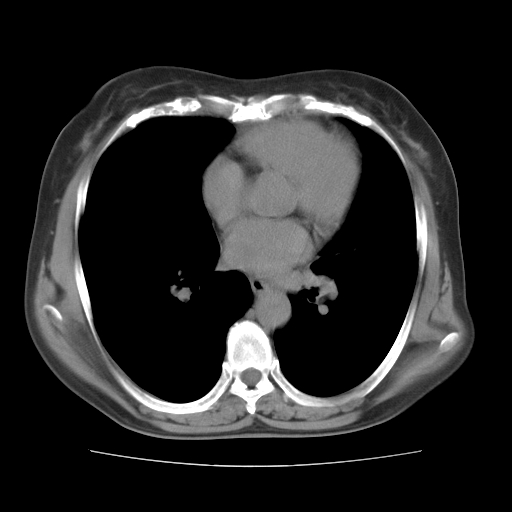

标题: CT10838:女性,56岁,是上腔静脉钙化还是淋巴结钙化?

女性,56岁临床诊断为胃贲门ca,术前检查发现,此钙化灶,对此科内稍有争论!请各位老师看看!是上腔的还是淋巴结的?有意义吗?

胸锁关节层面的是淋巴结钙化,气管前腔静脉后的钙化灶占了4个层面,不知层厚是多少?看样子应该是7--10毫米之间,那么这病灶最小纵径得有28毫米!应该提示点什么了,没传肺窗,估计肺内没有病变?

左锁骨下静脉和头臂静脉会合后形成是上腔静脉,此钙化位于两血管回合的腔静脉后方、气管右前方,这个位置没有其他结构,应该是淋巴结钙化。一般多为淋巴结核后钙化,没有临床意义。